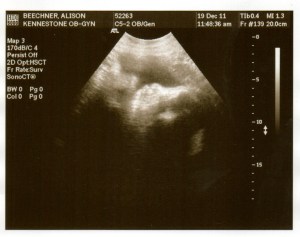

So I had an awesome day yesterday. First I went to the doc in the morning for my 32wk check-up. Just the usual, but as he was walking me out and talking about scheduling an ultrasound to figure out when we would need to do the c-section, the tech was hanging out there and said she could see me right then. so i got to go ahead and get the sonogram right then, and SURPRISE! my placenta has *completely* moved out of the way of my cervix and i have gone from a high-risk pregnancy requiring an early c-section to a completely normal pregnancy with no restrictions.

By now, your baby weighs 3.75 pounds (per an ultrasound she is actually 3 lbs, 9oz) and is about 16.7 inches long, taking up a lot of space in your uterus. You’re gaining about a pound a week (yup, gained two pounds since my last doc visit two weeks ago. was kinda bummed about that until i read this) and roughly half of that goes right to your baby. In fact, she’ll gain a third to half of her birth weight during the next 7 weeks as she fattens up for survival outside the womb. She now has toenails, fingernails, and real hair (or at least respectable peach fuzz). Her skin is becoming soft and smooth as she plumps up in preparation for birth.